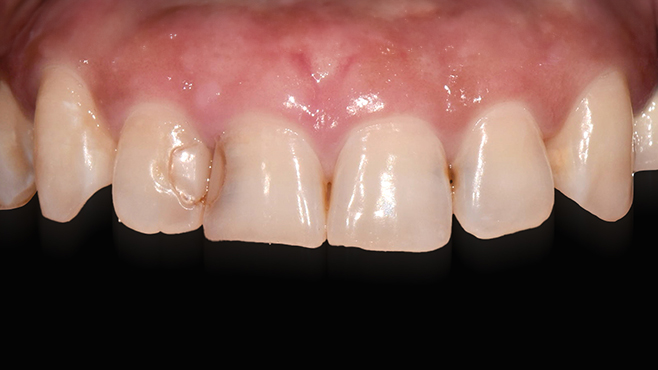

맞는 건 괜찮은데… 충치는 못 참겠습니다|20대 격투기 선수 치과 방문기